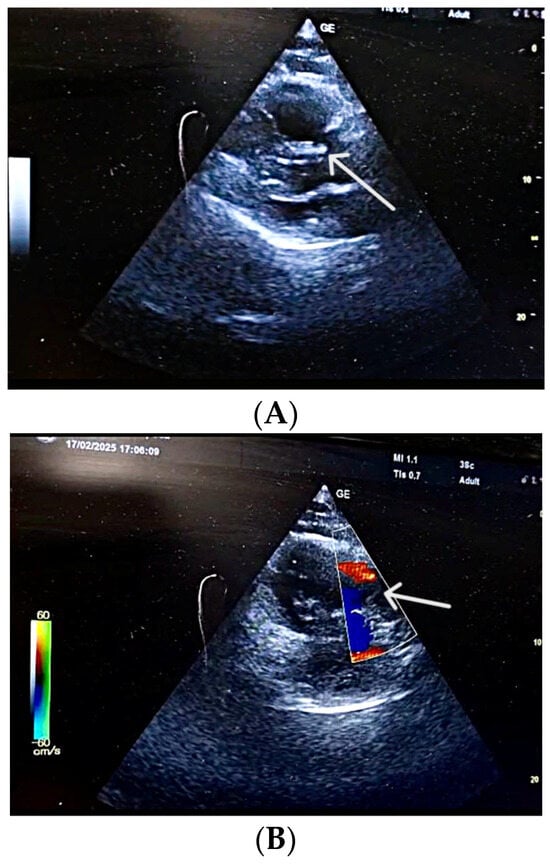

| Proximal DVT end | Lower third of superficial femoral vein | Non-adherent, unstable |

| Thrombus mobility | Free-floating, unstable | High embolization potential |

| Popliteal vein thrombosis | Nearly occlusive thrombus | Consistent with acute DVT |

| DVT extension | Distal into medial posterior tibial vein | Reflects propagation of DVT |